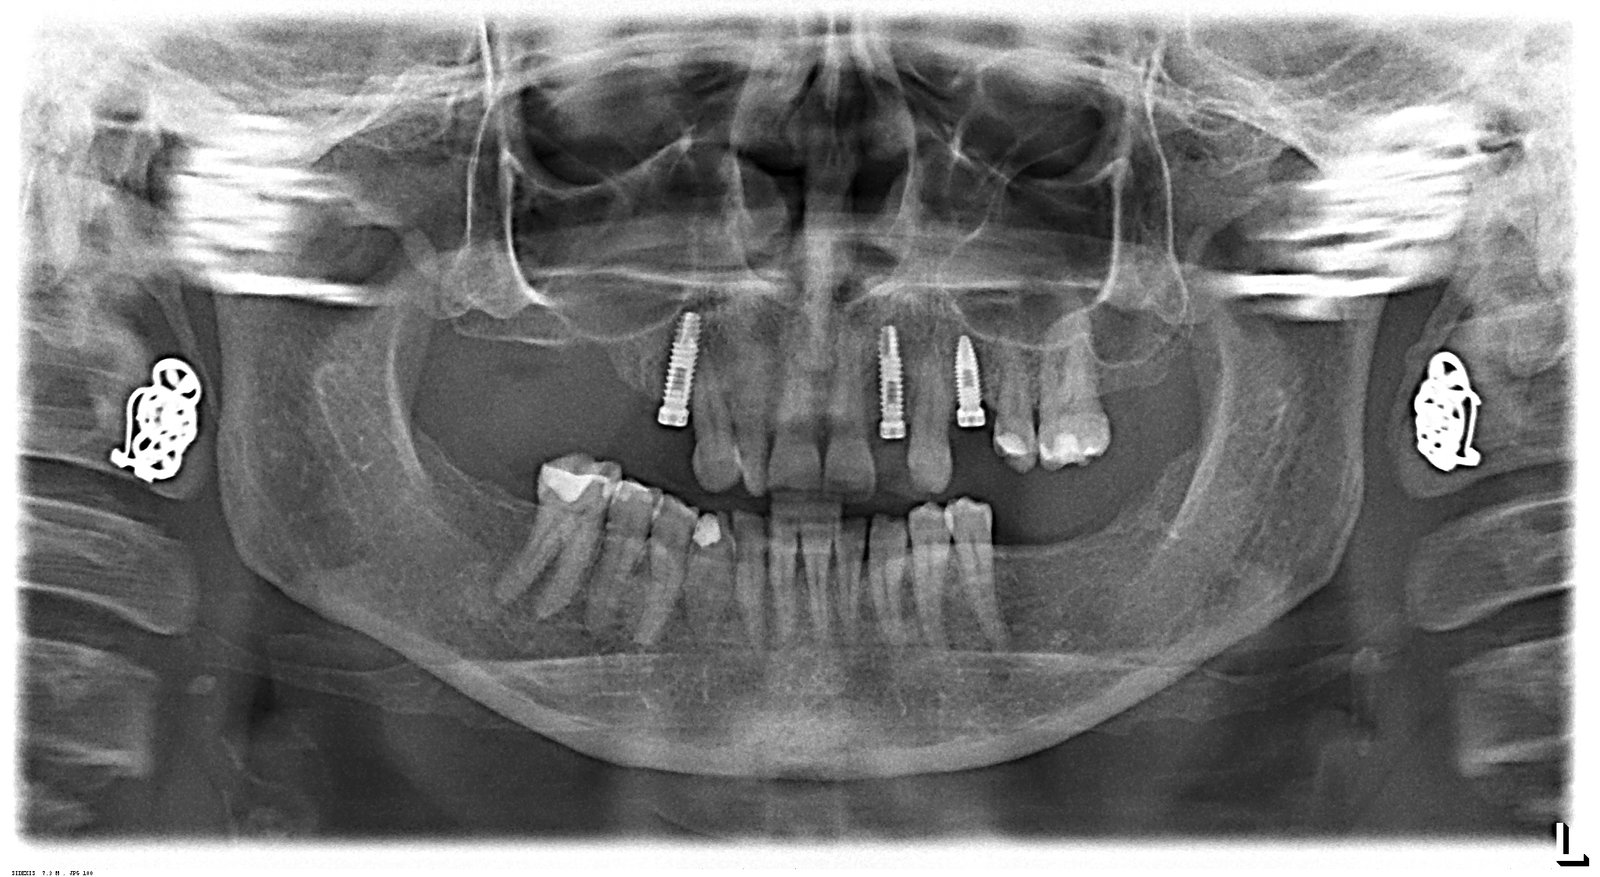

paciente que viene de iDental tengo que detectar los implantes para rehabilitarlo. Muchísimas gracias de antemano

Buenas tardes, Necesito ayuda con este caso. Es un paciente de idental, los implantes superiores se los colocaron antes del cierre. Hace unos 6 meses. Acudió a consulta con los [...]